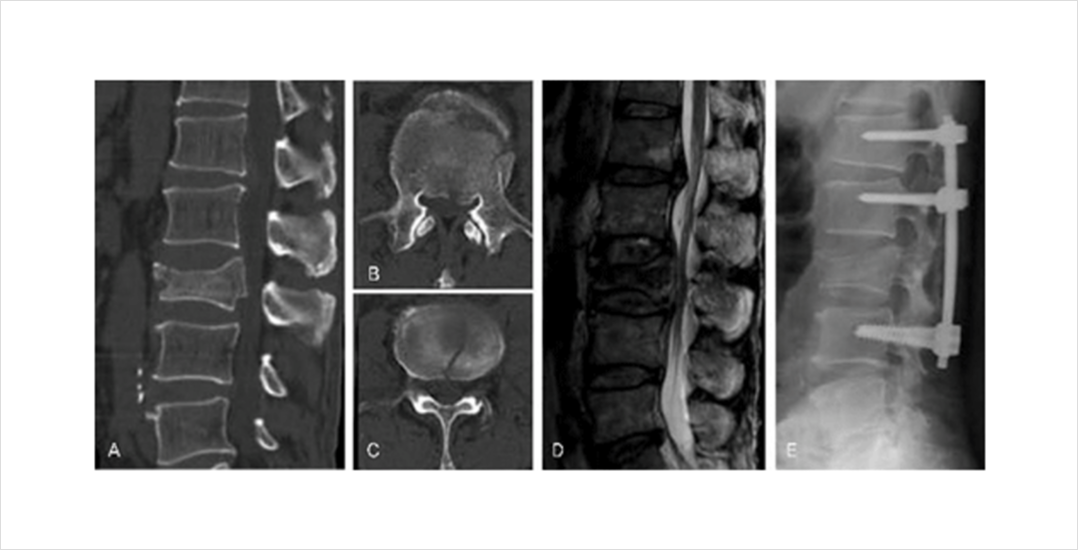

척추 골절이 심하여 골편이 신경을 압박하거나 골유합이 되지 않아 지속적인 불안정증이 있는 경우 척추체 고정술을 필요할 수 있습니다. 척추체 고정술이 필요한 경우에는 전문의와 자세한 상담이 필요합니다.

골다공증성 척추압박 골절이 제대로 치료되지 않는다면 척추체의 붕괴와 더불어 이로 인한 척추 후만 변형이 발생할 수 있습니다. 척추 후만 변형은 골다공증성 척추 압박 골절로 인한 척추체의 붕괴가 주로 척추의 앞부분에서 나타나기 때문입니다. 이는 골절의 회복 후에도 지속되는 허리통증 등의 후유증을 야기할 수 있습니다.

척추체 성형술을 시행하였지만 골시멘트와 유합이 일어나지 않고 척추체 내부에 괴사가 일어나면서 척추체의 붕괴가 진행되고 이로 인한 통증이 지속되는 경우도 있습니다. 이러한 경우에는 척추 불안정과 지속되는 통증을 해결하기 위해 척추체 고정술이 필요할 수 있습니다.